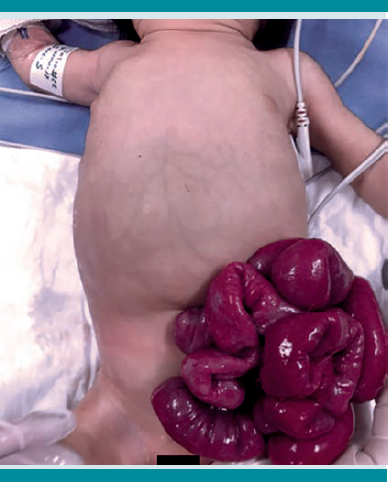

Desde el punto de vista clínico la paciente se encontró hemodinámicamente estable, la piel sobre la hernia se abrió dejando al descubierto las asas intestinales (Figuras 1 y 2). Los tejidos circundantes parecían edematosos, sin evidencia de infección o necrosis. El abdomen era suave y no distendido, sin datos de irritación peritoneal. El intestino eviscerado se cubrió con una gasa estéril empapada en solución salina.

Los reportes de los exámenes de laboratorio y gasometría sin alteraciones. En las radiografías toracoabdominal antero-posterior y lateral de abdomen (Figuras 3 y 4) se observó una canica en la cavidad abdominal. Con lo anterior se estableció el diagnóstico de ruptura de saco herniario umbilical asociada con la colocación de un cuerpo extraño, con evisceración.

Se realizó intervención quirúrgica de urgencia, con plastia e introducción de las asas intestinales, sin contratiempos ni complicaciones (Figura 5 y 6). Los hallazgos quirúrgicos revelaron la existencia de un objeto extraño en la cavidad (canica) y las asas del intestino delgado evisceradas. El tamaño del defecto de la pared era de 2 cm de diámetro, a la altura del ombligo.